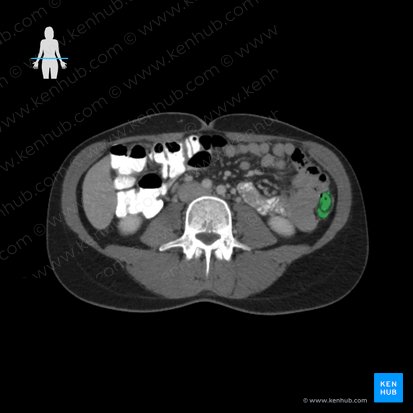

Descending colon

The descending colon is a segment of the large intestine positioned within the left paracolic gutter of the posterolateral abdominal wall. It extends from the left hypochondriac region and runs through the left flank to reach the left iliac fossa. Beginning at the left colic flexure proximally, it descends vertically and becomes continuous with the sigmoid colon distally.

In adults, the descending colon measures about 25–30 cm. It is a retroperitoneal organ, with its anterolateral surface covered by parietal peritoneum that attaches it to the posterior abdominal wall. It runs anterior to the lateral border of the left kidney and in about a third of people, the distal portion of the descending colon has a short mesentery.